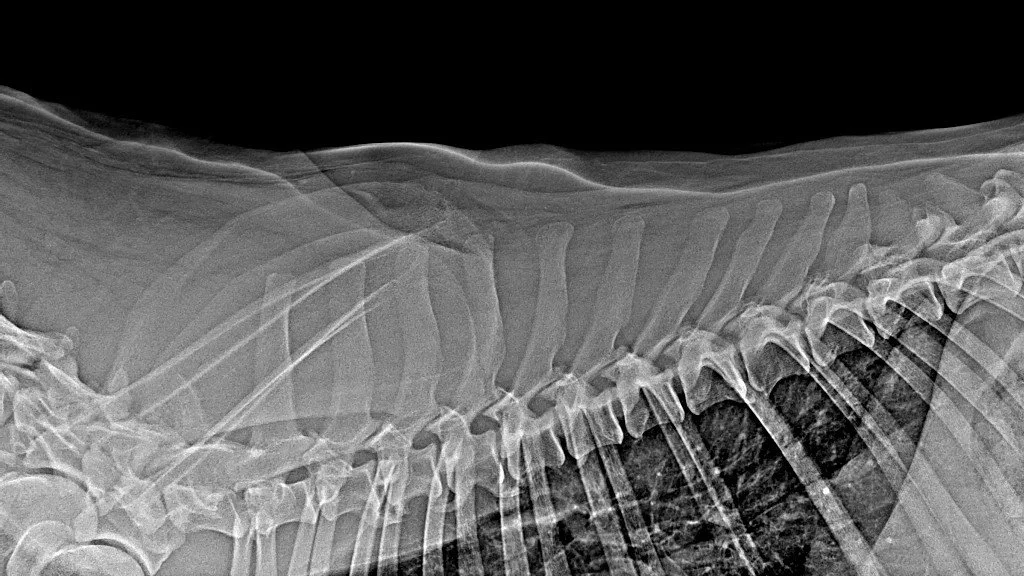

x-ray with awake patient was performed on forelimb (medio-lateral view of elbows and dorso-palmar view of carpus) and latero-lateral view of thoracic and lumbar vertebrae.

Radiographic findings consisted of severe left elbow dysplasia, in addition to spondylarthrosis (thoracic vertebrae and thoraco-lumbar region)